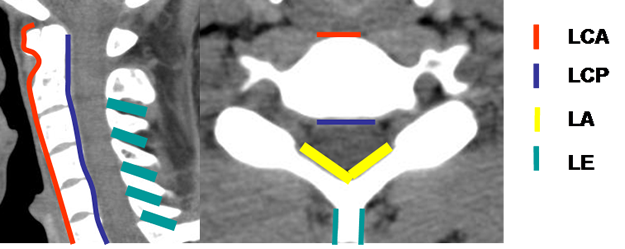

Hay múltiples ligamentos que estabilizan la columna. Los ligamentos longitudinal común anterior (LLCA) y posterior (LLCP) que fija los cuerpos vertebrales, el ligamento amarillo que une las láminas, los ligamentos intertransversos, interespinosos, etc. (3). (Fig 3).

Fig 3. Diagrama ligamentos.

A: TAC reconstrucción sagital y B: TAC axial. LCA: Ligamento común anterior.

LCM: Ligamento común posterior. LA: Ligamento amarillo. LE: Ligamento interespinoso.